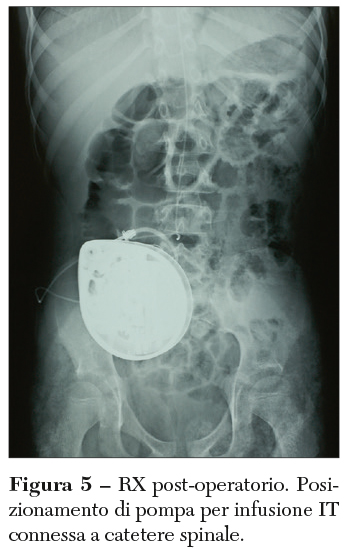

In molti casi, l’impianto del reservoir collegato al catetere spinale è preferito rispetto alla puntura lombare, spesso di difficile esecuzione nei pazienti affetti da spasticità, anche perché il reservoir permette la ripetizione del test a dosi crescenti quando necessario. Il test viene somministrato ai pazienti affetti da spasticità grave, generalizzata, non altrimenti correttamente controllata, che limita la qualità della vita, la cui massa corporea sia adeguata a tollerare l’impianto. È inoltre fondamentale la disponibilità del paziente e dei caregivers a proseguire con questo iter. Una volta eseguito l’impianto, infatti, sarà necessario provvedere a periodici controlli per valutare l’efficacia del farmaco e la adeguatezza della posologia, per eseguire il re-filling della pompa e provvedere alla sostituzione della pompa stessa al termine del funzionamento della sua batteria. L’impianto della pompa definitiva consiste nell’inserire un catetere di infusione spinale sotto controllo radiologico per verificare il raggiungimento del livello spinale desiderato (possibilmente cervicale o toracico alto quando si desideri ottenere un controllo della tetraparesi spastica; toracico basso-lombare alto nelle diplegie spastiche). Successivamente questo catetere viene collegato alla pompa di infusione a rilascio programmato o a flusso fisso, che viene alloggiata in addome (Figura 5).